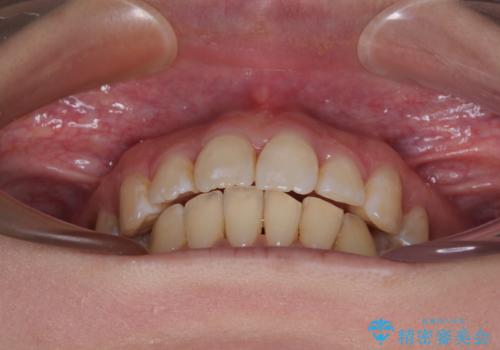

出っ歯を治したい ワイヤー装置での抜歯矯正で劇的変化!

どこまで口元の突出感を改善できるのか不安でしたが、舌のトレーニングをしっかりと行ってくださり、我々も驚くほど劇的に改善することができました。